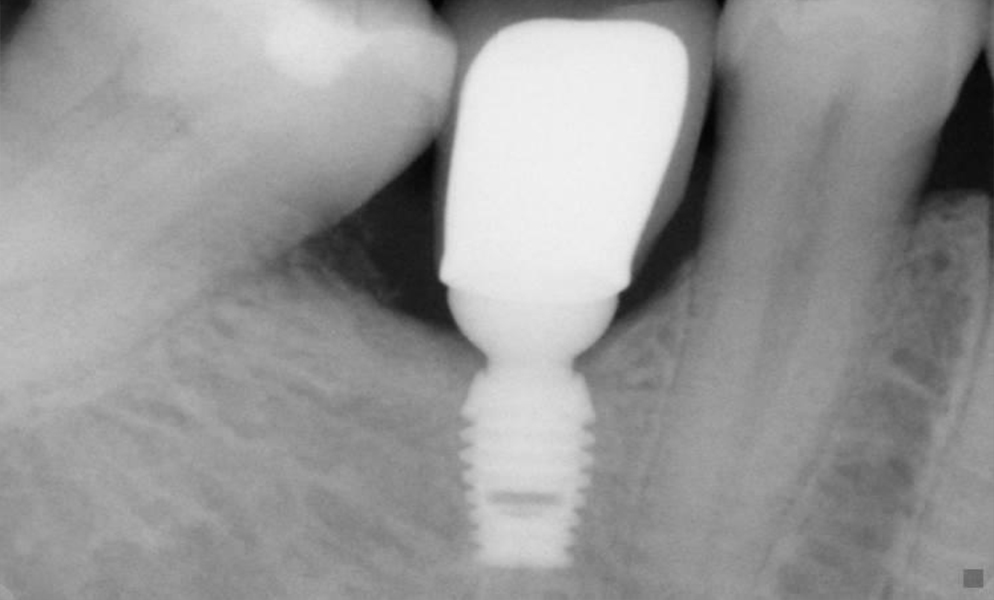

| Before | After |

![]() |

| Single posterior tooth missing space restored with a 4x6 mm short dental implant (Bicon, USA) to avoid sinus lift and bone graft procedures | |